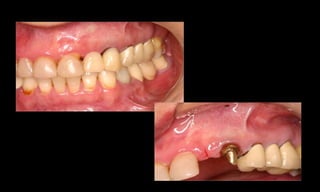

Benefícios do Sistema Cone Morse

Baixo potencial para perda óssea marginal

(Tenenbaum et al. Impl Dent, 2003);

Resultados estéticos periimplantares otimizados

(Abboud, M. IJOMI, 2005).

10-10-2005

Novembro de 2005

24-01-2006